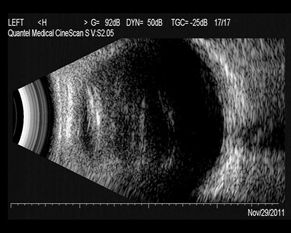

2、玻璃体混浊是什么意思玻璃体混浊是一种眼部疾病,又称飞蚊症,是玻璃体受周围组织受病变的影响而发生的变性、出血、渗出等病理变化,表现为玻璃体浑浊、液化、纤维膜的形成和收缩。

3、3 概述 玻璃体内透明的凝胶体,如果出现不透明体,就称为玻璃体混浊(vitreous opacities)。4 诊断 症状 ①发病突然,常有反复。②眼前出现烟柱式或黑云状暗影,有的很快失明,仅留光感。

4、玻璃体混浊就是指玻璃体内透明的凝胶体,出现不透明体即混浊。